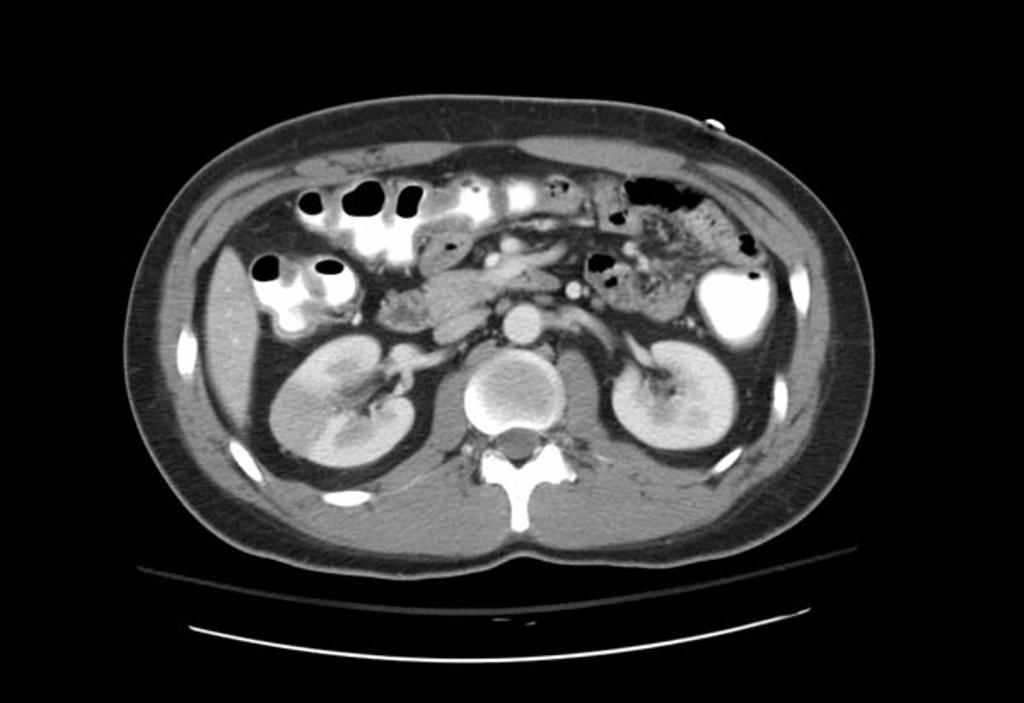

You order a CT abdomen/pelvis with IV contrast after discussing the patient with your radiologist, and the result is surprising: a right-sided renal infarction with extensive thrombus in the right renal artery! With these results, you immediately call your surgeon and interventional radiologist.

As these patients will often present with a classic history for AAA and AAA risk factors, performing a quick bedside US is crucial. If the US is negative, often the next step would be CT with no contrast. If both CT and US are negative, then order CT with IV contrast, as long as the patient’s GFR is above 60 (though this is controversial and will not be covered; see past www.emdocs.net post on this topic). The classic finding on CT with IV contrast is a wedge-shaped perfusion defect.4 Other options include radioisotope scan, which is not often feasible with today’s imaging, and MRI, but this requires gadolinium enhancement which is associated with nephrogenic systemic fibrosis in patients with decreased renal function. Ultrasound of the kidneys and renal vessels unfortunately does not have the necessary sensitivity to rule out the diagnosis.